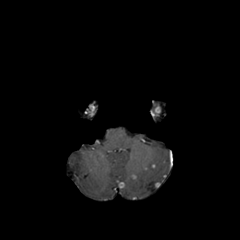

Objectives: This work aims to explore the impact of multicenter data heterogeneity on deep learning brain metastases (BM) autosegmentation performance, and assess the efficacy of an incremental transfer learning technique, namely learning without forgetting (LWF), to improve model generalizability without sharing raw data. Materials and methods: A total of six BM datasets from University Hospital Erlangen (UKER), University Hospital Zurich (USZ), Stanford, UCSF, NYU and BraTS Challenge 2023 on BM segmentation were used for this evaluation. First, the multicenter performance of a convolutional neural network (DeepMedic) for BM autosegmentation was established for exclusive single-center training and for training on pooled data, respectively. Subsequently bilateral collaboration was evaluated, where a UKER pretrained model is shared to another center for further training using transfer learning (TL) either with or without LWF. Results: For single-center training, average F1 scores of BM detection range from 0.625 (NYU) to 0.876 (UKER) on respective single-center test data. Mixed multicenter training notably improves F1 scores at Stanford and NYU, with negligible improvement at other centers. When the UKER pretrained model is applied to USZ, LWF achieves a higher average F1 score (0.839) than naive TL (0.570) and single-center training (0.688) on combined UKER and USZ test data. Naive TL improves sensitivity and contouring accuracy, but compromises precision. Conversely, LWF demonstrates commendable sensitivity, precision and contouring accuracy. When applied to Stanford, similar performance was observed. Conclusion: Data heterogeneity results in varying performance in BM autosegmentation, posing challenges to model generalizability. LWF is a promising approach to peer-to-peer privacy-preserving model training.